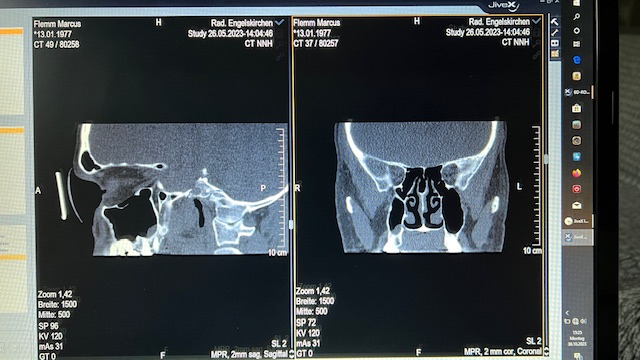

Im Winter 2022 bekam ich einen grippalen Infekt und im Februar 2023 Covid. Daraufhin bekam ich Schmerzen im rechten Oberkiefer. Es handelte sich um einen drückenden Schmerz, der zeitweise auch ziehend war. Ich hatte Sorge wegen meiner zwei Implantate und ließ meinen MKG dies prüfen. Er machte ein DVT (s. angefügte Bilder – (der Titan-Pin zur Fixierung beim Eingriff ist noch im Knochen – siehe Bild)) und konnte einen Sekretspiegel in der rechten Kieferhöhle finden. Diesen Spiegel konnte ich auch beim Kopf vorbeugen bzw. in den Nacken legen gefühlt vor- und rückwärts “schwappen” lassen. Er führte dies auf die vorherigen Infekte und hielt dies für unbedenklich für die Zähne bzw. Implantate. Er verschrieb mir dennoch Amox wegen der Schmerzen. Dies führte jedoch nicht zum Erfolg. Daraufhin überwiess er mich mit Verdacht auf Sinusitis in den Fachbereich HNO.

Hier wurde nach Nasenendoskopie auch chronische Sinusitis vermutet, da ich auch Allergiker (Birke und Gräser) bin. Hieraufhin wurde im Mai 2023 ein CT gemacht (s. exemplarische Bilder). Der Anblick der Bilder bestätigte aber keine Sinusitis, sondern die Annahme meines MKG von Sekretresten der Infekte. Es wurden 3 Monate tägliche Nasendusche mit Emsersalz, Kortisonnasenspray und Nasensalbe verordnet. Die Situation mit dem Sekret wurde besser. Das “Schwappen” war weg. Das Sekret laut HNO im Griff. Ich wurde aus dem HNO Bereich entlassen.

CT (Mai 2023):